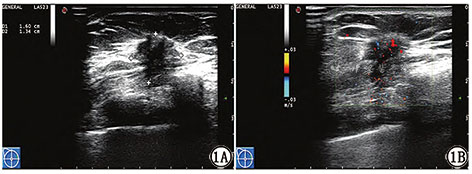

Clinical study of ultrasonic signs and molecular biological indicators of senile non-specific invasive breast cancer

To investigate the correlation between ultrasound signs and the expression of estrogen receptor (ER), progesterone receptor (PR), human epidermal growth factor receptor-2 (HER-2), Ki67 antigen and other molecular biological indicators in elderly non-specific invasive breast cancer (IBC-NST).

The MRI findings (mass size, shape, margin, microcalcification, blood flow distribution) and molecular biological indicators of 82 patients with pathologically confirmed IBC-NST from May 2017 to August 2019 were retrospectively analyzed. SPSS21.0 statistical software was used for analysis. The counting data were represented by [n (%)] and tested. Measurement data were expressed as () and t test was adopted. P<0.05 was considered to be statistically significant.

The tumor size was correlated with the positive expression of ER, PR, HER-2 and Ki-67, the burr sign of tumor margin was correlated with the positive expression of ER and PR, and the microcalcification in tumor was correlated with the positive expression of HER-2 and Ki-67 (P<0.05). Tumor morphology, posterior echo and blood flow distribution were not significantly correlated with the expression of ER, PR, HER-2 and Ki-67 (P> 0.05).

IBC-NST ultrasound signs are obviously correlated with molecular biological indicators. By analyzing the ultrasonic characteristics of IBC-NST, the biological behavior of tumor can be evaluated, and it has certain reference value for guiding clinical treatment and judging prognosis.